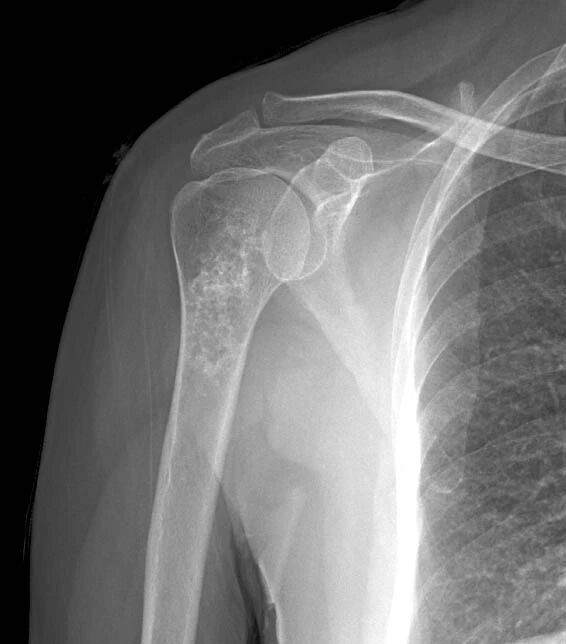

瘤软骨常表现为环状钙化, 是诊断软骨类肿瘤较为可靠的影像学征象。环状钙化形成于环状软骨、以及软骨小叶边缘的软骨基质。钙质沉着可呈小点状、小条状、半环状或弧形;亦可浓密相连、重叠呈菜花状。钙化环的形态和密度可反映瘤组织分化程度, 通过观察钙化环的形态和密度,有助于良恶肿瘤的鉴别。良性瘤软骨之瘤细胞分化好、生长缓慢、血供充分, 钙化环完整,密度高, 边缘清楚。良性软骨类肿瘤如骨软骨瘤(图 35)、软骨母细胞瘤(图 36)、内生软骨瘤(图 37)等均可于瘤组织内发生环形钙化。恶性瘤软骨则呈密度淡薄, 边缘模糊的不规则钙化,恶性骨肿瘤的环形钙化,最多见于软骨肉瘤(图 38),其次是骨肉瘤。CT 是发现肿瘤内软骨钙化最为敏感的检查方法。

图 38.瘤软骨钙化:软骨肉瘤